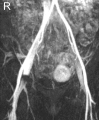

Acetabular labral tears are a known cause of hip pain in the young, active patient. Labral tears can be due to trauma, femoroacetabular impingement, capsular laxity, dysplasia, and degenerative pathology. Paralabral cysts are relatively common in association with labral tears of the hip, with cysts seen on magnetic resonance imaging studies in as many as 50% to 70% of patients with labral tears. In some cases the cysts can become sizeable and cause neurovascular compression. Nonoperative interventions for the management of paralabral cysts in the shoulder and knee have shown high recurrence rates. In the shoulder and knee, arthroscopic debridement of paralabral cysts has shown good results with lower recurrence rates and resolution of neurovascular function. In the hip there is limited literature regarding surgical management of paralabral cysts. We present a surgical technique for arthroscopic decompression of acetabular paralabral cysts combined with labral repair.